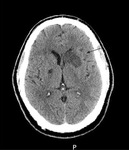

Acidente vascular cerebral (AVC) isquêmico

Tomografia computadorizada (TC) de crânio sem contraste mostrando infarto ganglionar basal isolado esquerdo subagudo com efeito de massa protuberante frontal esquerda

Cortesia do BMJ Case Reports 2009; (doi:10.1136/bcr.10.2008.1139)